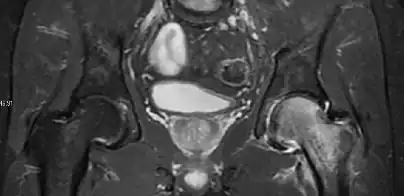

Synovial chondromatosis can be confidently diagnosed by X-ray when calcified cartilaginous chondromas are seen. However, other synovial proliferative processes, such as pigmented villonodular synovitis, require MRI for accurate diagnosis, although noncalcified synovitis can be suspected in radiographs by indirect signs, such as soft tissue swelling and/or erosions in the femoral head, femoral neck, or acetabulum (Figure 7).[1]

Figure 7:

-

Axial CT image of pigmented villonodular synovitis eroding the posterior cortex of the femoral neck.[1] -

Sagittal T2* gradient echo image showing a posterior soft tissue mass with hypointense areas secondary to hemosiderin deposition.[1] -

X-ray of synovial chondromatosis.[1] -

CT of synovial chondromatosis.[1]

In synovial proliferative disorders, MRI demonstrates synovial hypertrophy. In the case of PVNS, characteristic foci of low signal intensity related to hemosiderin deposition are better seen on gradient echo T2* images (Figure 7). In the case of synovial osteochondromatosis, the synovial hypertrophy is accompanied by intermediate signal cartilaginous loose bodies and/or low signal calcified loose bodies.[1]